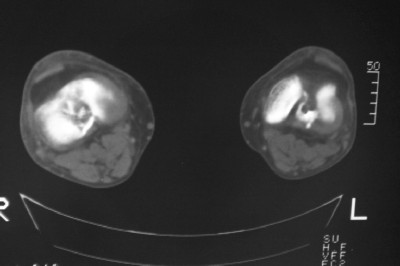

标题: CT8024:会诊!!!男 60 岁 双漆关节疼痛半年,进行性加重 [打印本页]

患者男 60 岁 双漆关节疼痛半年,进行性加重.

左侧股骨下端骨梗死

右股骨内髁关节面下多个不规则小囊变,边缘有明显硬化边,.......考虑: 1.关节面下骨囊变.  2.类风湿关节炎?   3.血友病?

右侧髁间隆突变尖,软骨下假囊肿形成,结合病人年龄较大,首先考虑退行性骨关节病。关节周围软组织未见明显异常,病人单单一双膝关节出现症状,不太支持类风湿性关节炎,可结合化验室检查。